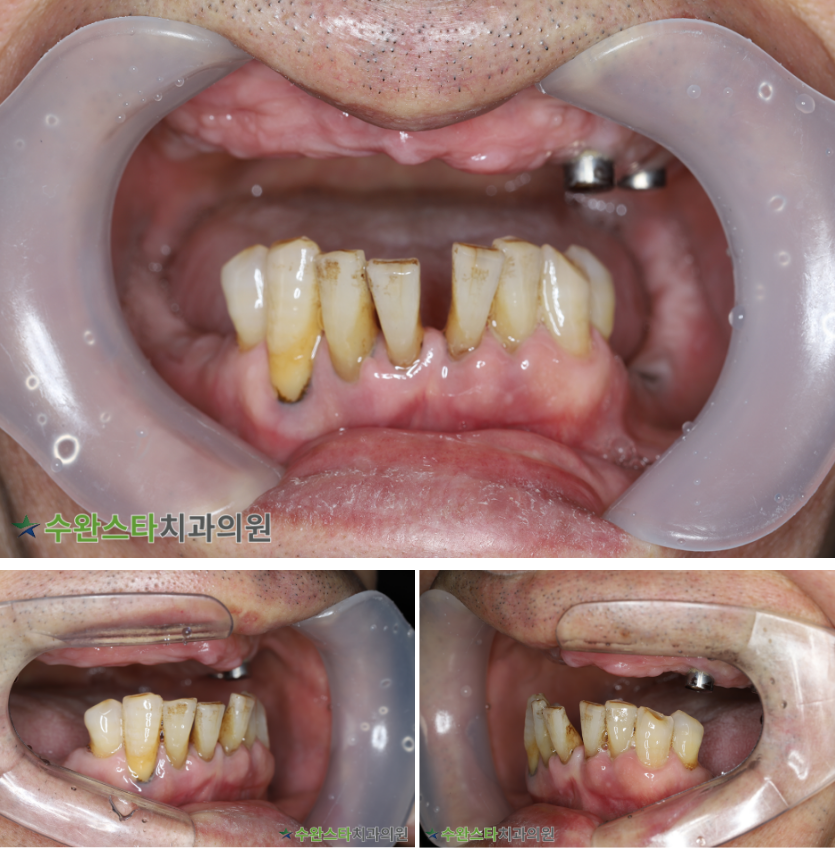

내원 시 상태

처음 내원 시 구강 내부 사진, 60대 남성 (2025. 12 촬영)

내원 시 환자분의

구강 내부 사진입니다.

틀니를 사용하신지

오래되었다고 합니다.